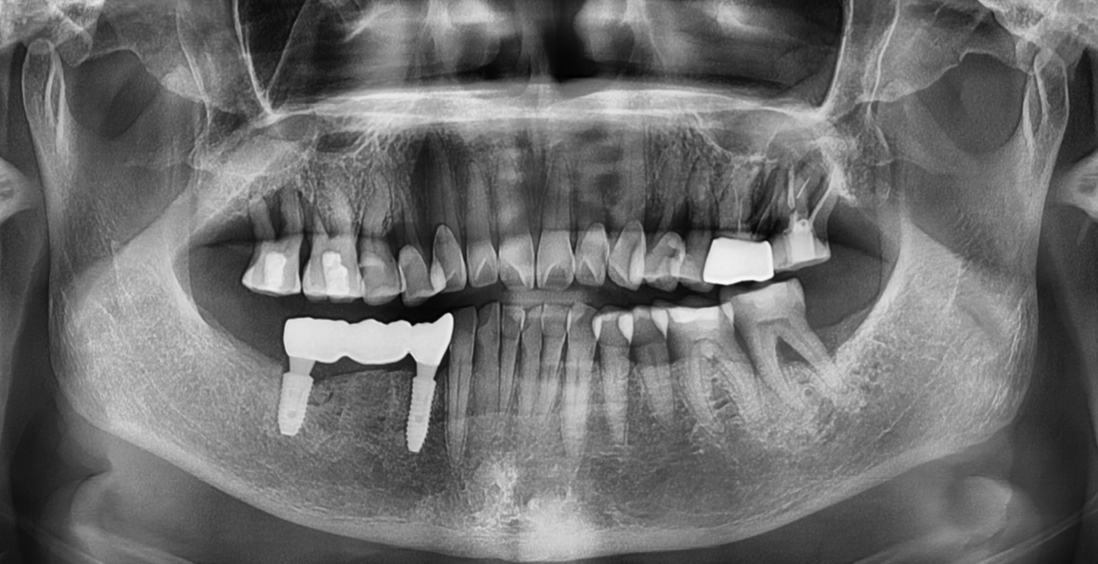

CASE 1 : 뼈이식 임플란트 (치료기간 : 8개월)

*치료과정에서 부작용이 발생할 수 있으므로

정확한 진단과 수술이 요구됩니다.

BEFORE

AFTER